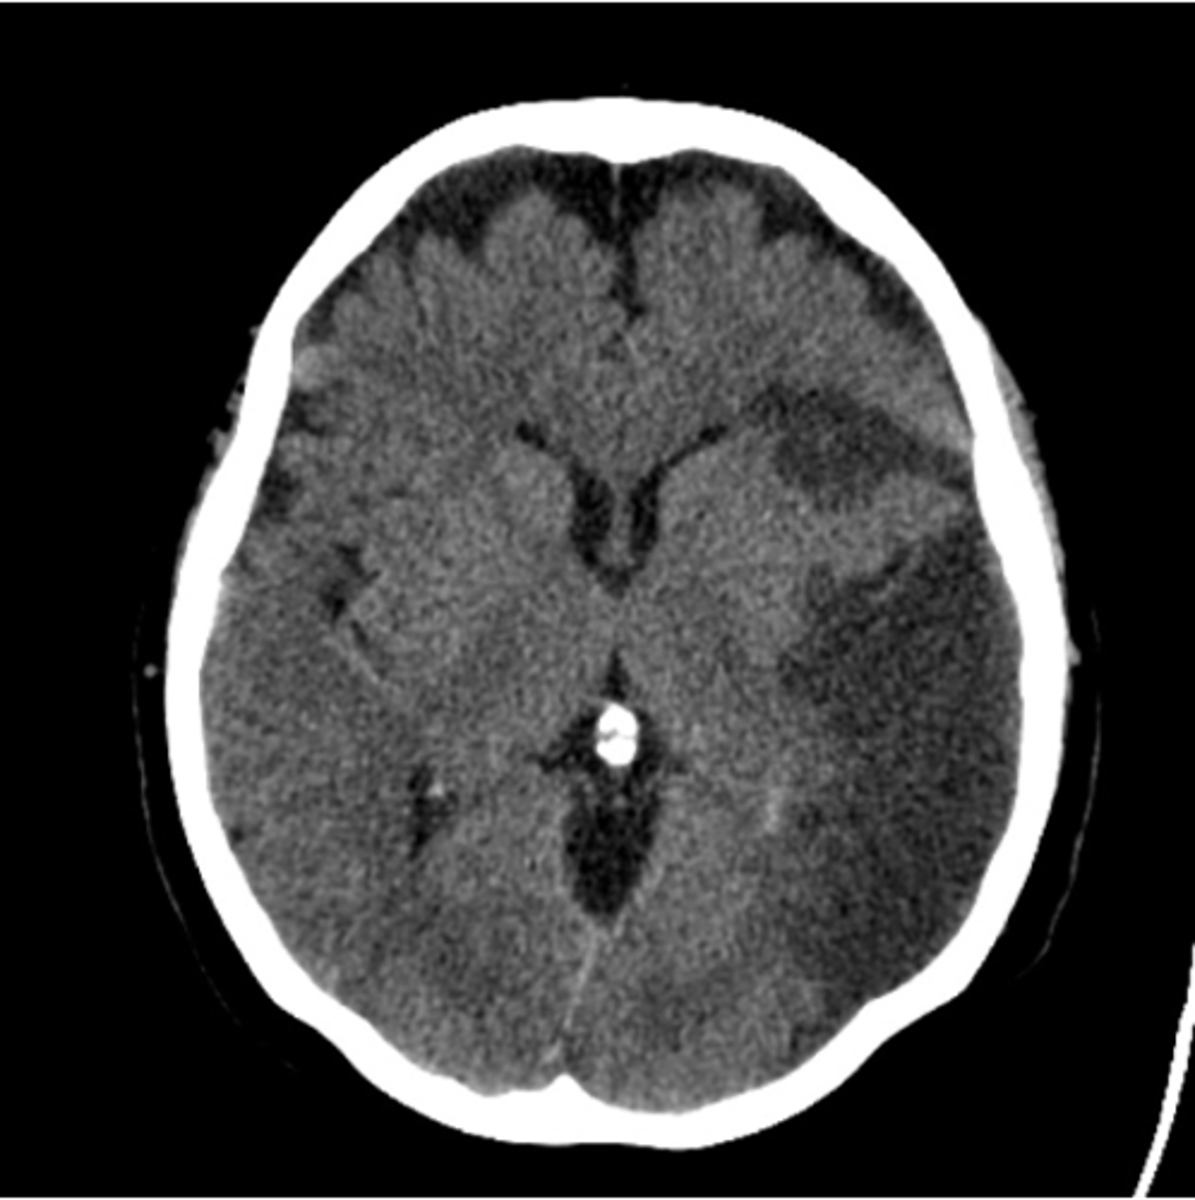

"Dry" CT

CT w/o IV contrast

CT w/o contrast can help identify

intracranial bleeding, stroke (ischemic or hemorrhagic), brain/spine tumors, fractures, spinal stenosis

Dark (on CT) means

White means